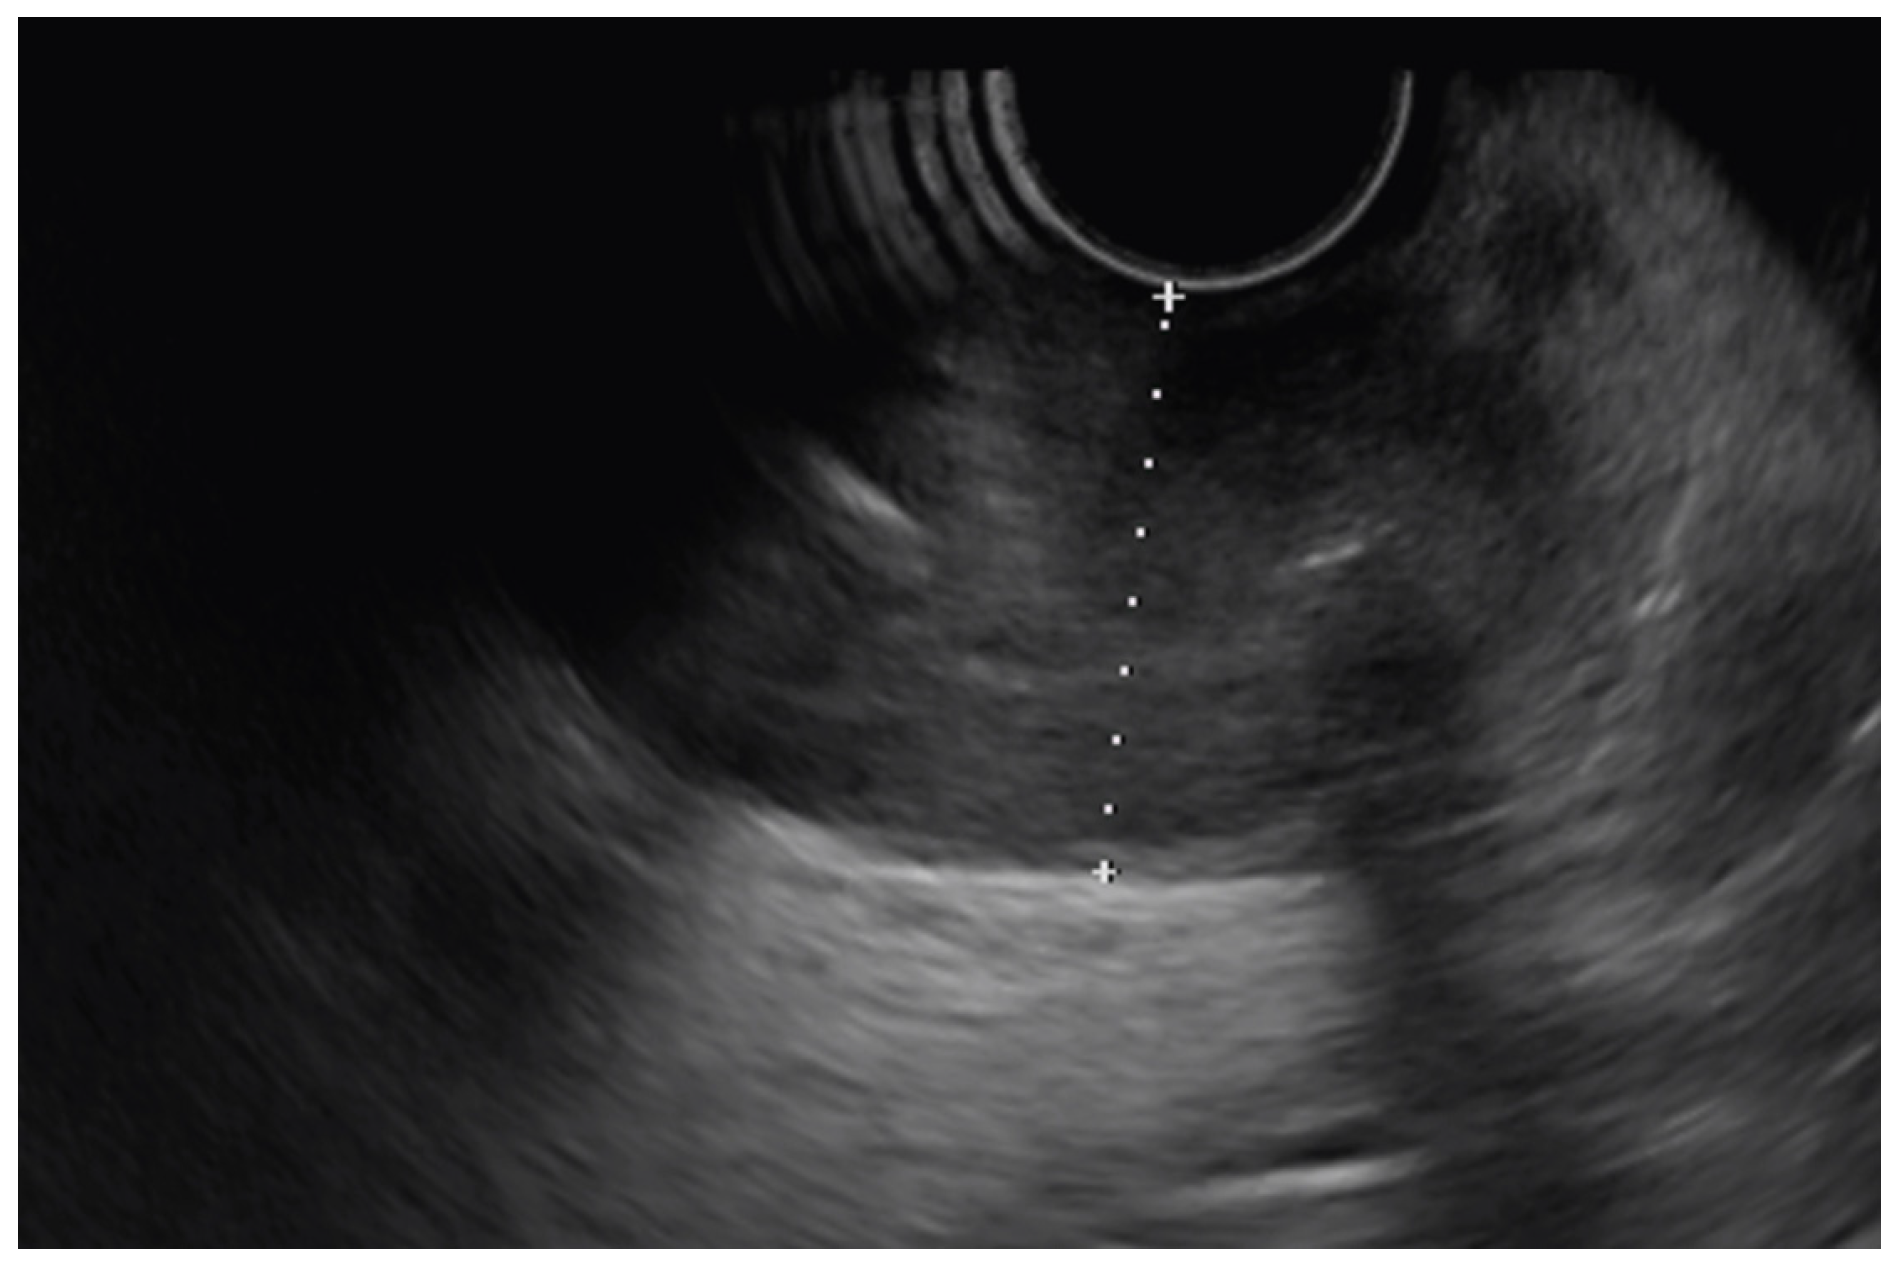

6.4. EUS in Gastric Linitis Plastica

6.5. Gastric Subepithelial Lesions

- Andriulli, A.; Recchia, S.; De Angelis, C.; Mazzucco, D.; Berti, E.; Arrigoni, A.; Verme, G. Endoscopic ultrasonographic evaluation of patients with biopsy negative gastric linitis plastica. Gastrointest. Endosc. 1990, 36, 611–615. [Google Scholar] [CrossRef]

- Shan, G.-D.; Xu, G.-Q.; Li, Y.-M. Endoscopic ultrasonographic features of gastric linitis plastica in fifty-five Chinese patients. J. Zhejiang Univ. B 2013, 14, 844–848. [Google Scholar] [CrossRef] [PubMed][Green Version]

- Aujla, U.I.; Jabbar, S.; Atique, M. Gastric Linitis Plastica and role of endoscopic ultrasound: An under-recognised diagnostic modality. J. Pak. Med. Assoc. 2022, 72, 174–176. [Google Scholar] [CrossRef] [PubMed]